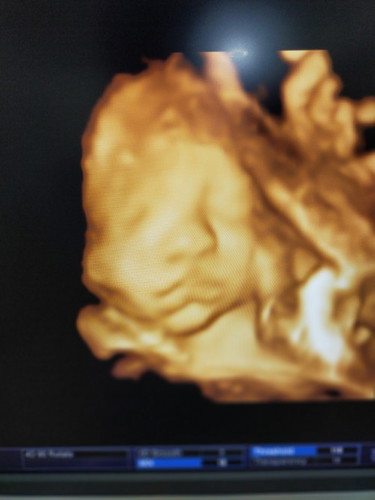

ภาวะปากแหว่งเพดานโหว่

แม่ๆช่วยดูหน่อยค่ะว่าปากน้องเป็นภาวะปากแหว่งเพดานโหว่ไหมค่ะ ลืมถามคุณหมอคะ

ของเราหมอจะเเจ้งเเละเขียนที่ใบว่าไม่พบปากเเหวงค่ะ..ดูจากน่าเเละปากน้องเเล้วปกตินะค่ะ

ถ้าซาวด์แบบนี้ ถ้าผิดปกติหมอจะแจ้งนะคะ